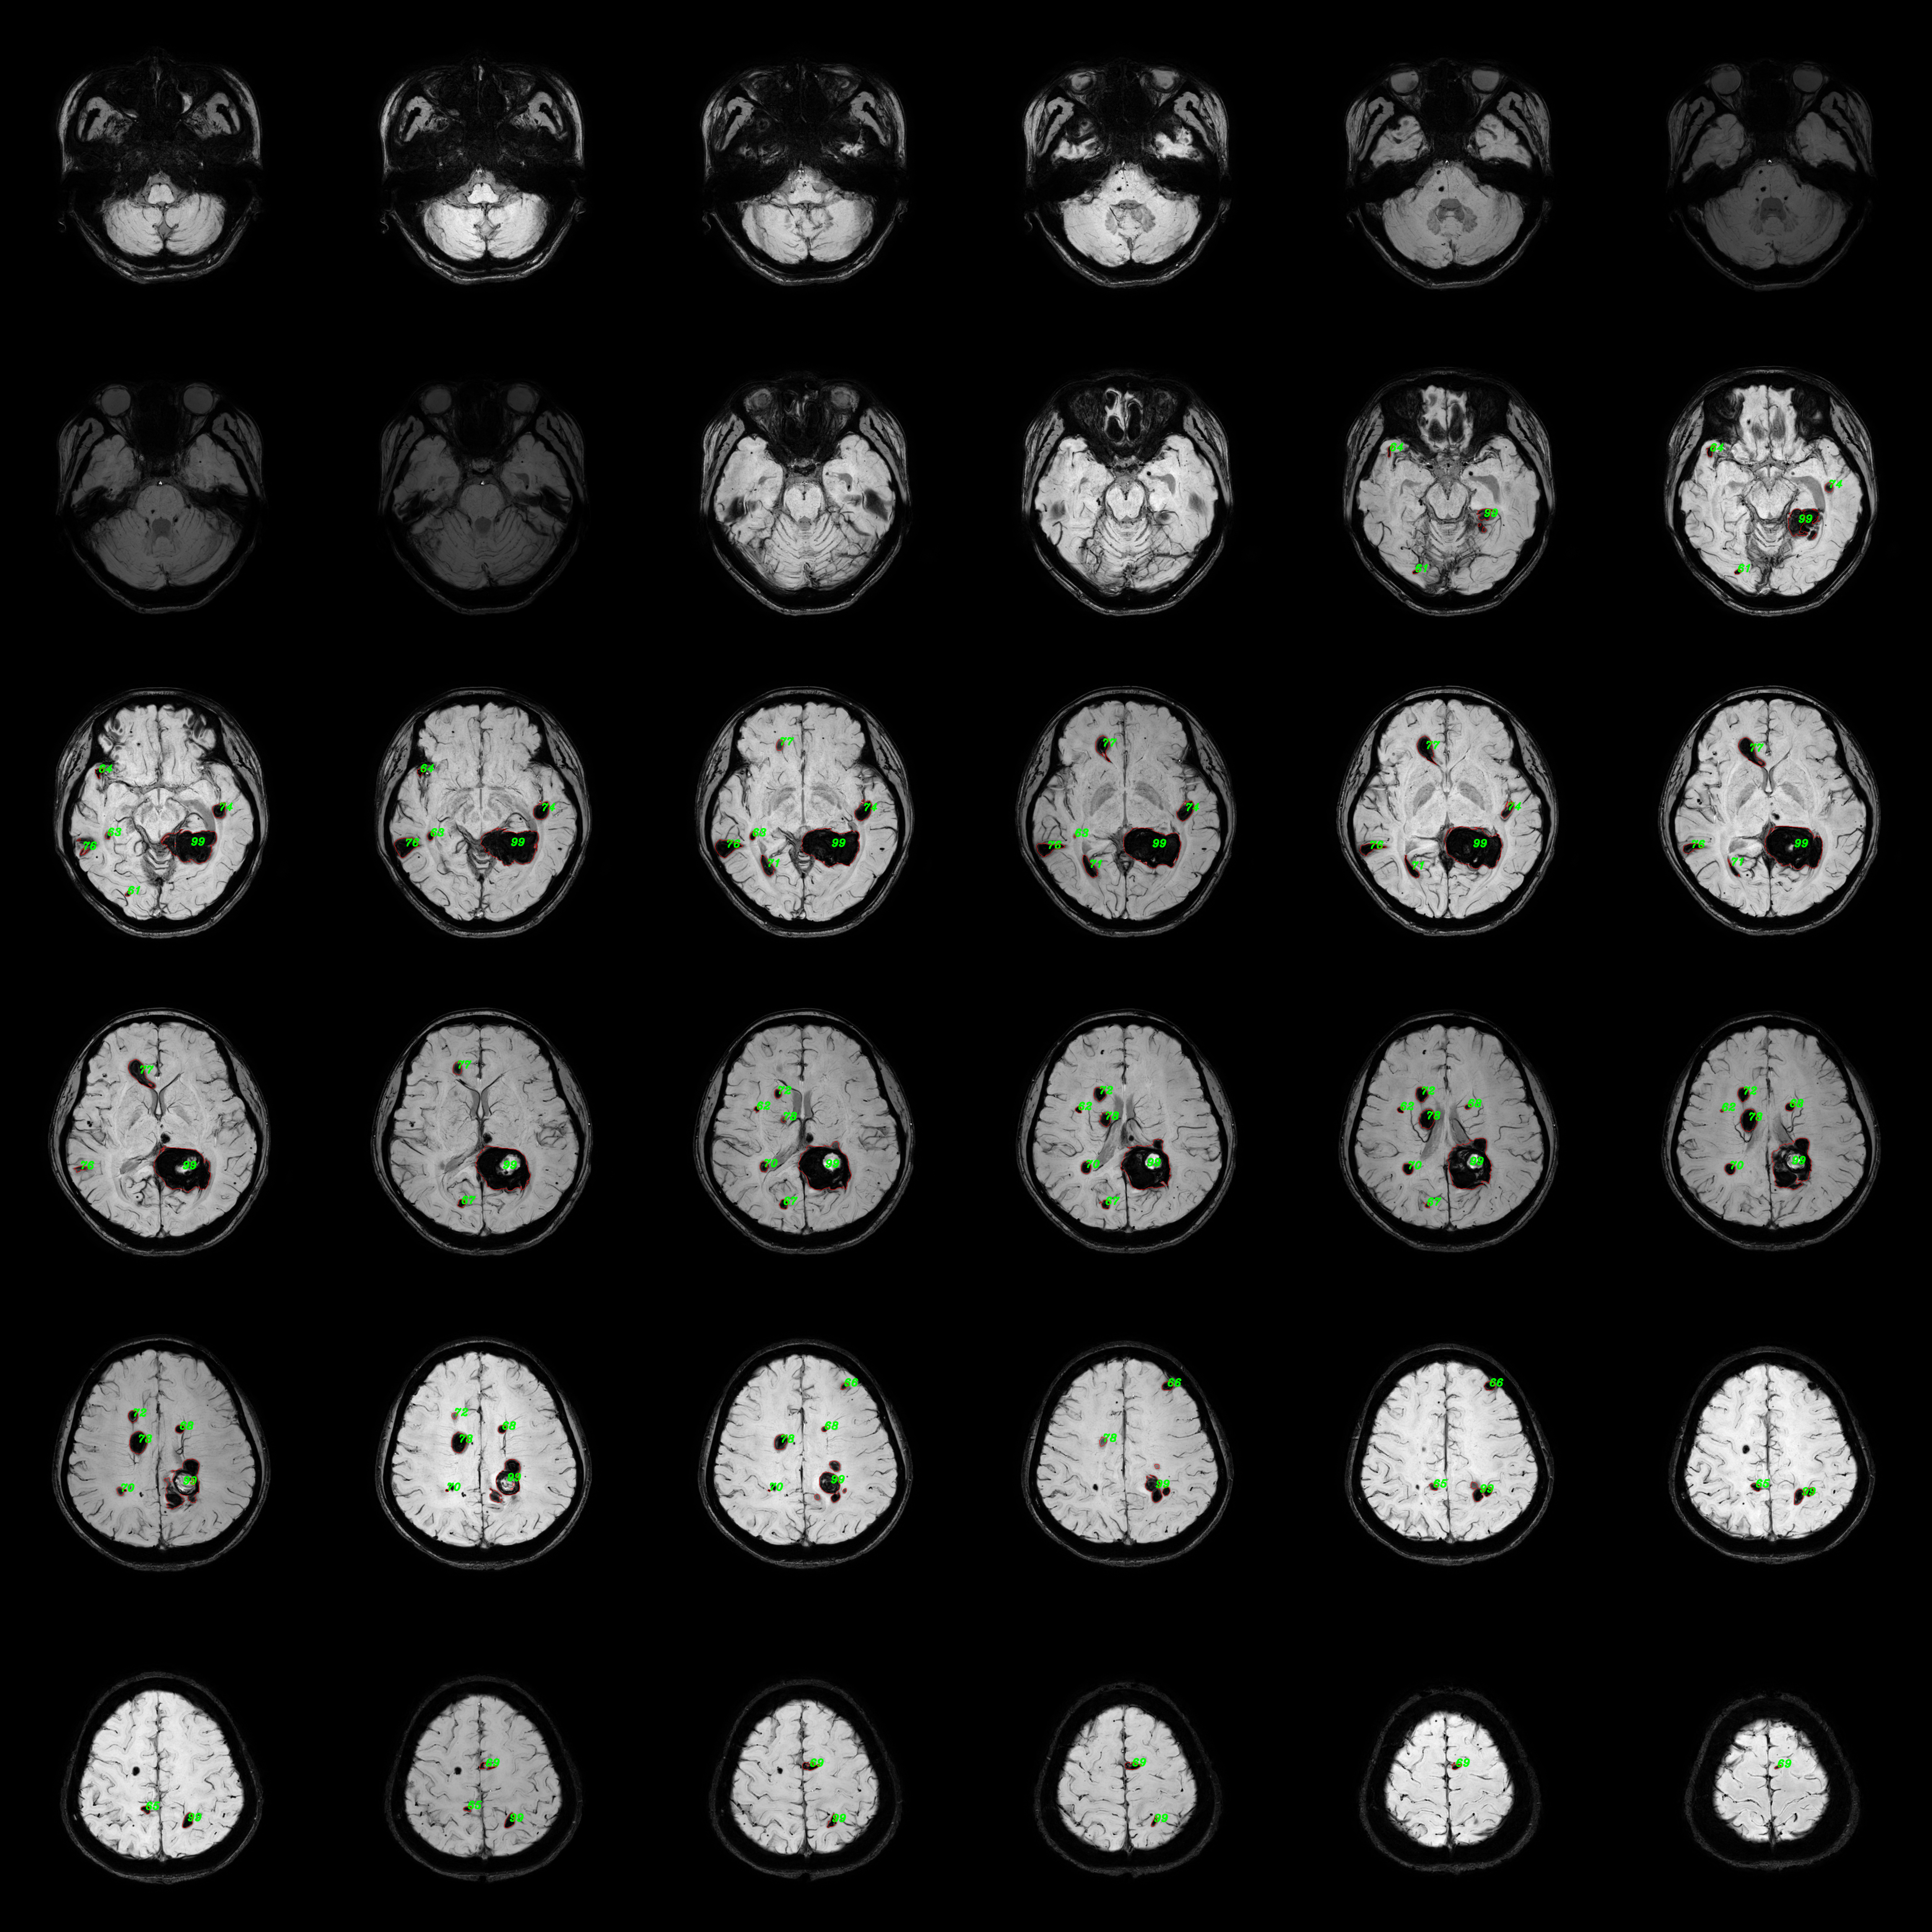

Refer to caption

Figure 7: Quantitative analysis visualization collage. This example consists of consecutive images from four planes of cranial MRI SWI sequences for two inspections of one patient. Numerals correspond to the indexes of the respective 3D lesion bodies. The red contour represents the visualization of the contours of the lesion segmentation predicted masks.

4.3 Quantitative statistics results

In the FCCM lesion quantitative statistics module, 2D segmentation results of lesions were first acquired, and then a 3D segmentation mask was synthesized for quantitative statistics. The statistical information included the number and volume of lesions, and a comparative statistics of lesions between two examinations of the same patient was conducted. The quantitative statistical results of a case were presented to demonstrate the effectiveness of the proposed lesion quantitative statistical module. Figure 7 showed the results of quantitative analysis visualization, where the numbering of each lesion and the contour of the lesion segmentation mask were plotted on the original FCCM image. The visualization collages of the entire volumes were shown in Figure 2 and Figure 3 in the Appendix A. The numberings and corresponding volume/volume pairs of lesions with a volume greater than 100 were presented in Table 3. The shaded areas depicted multiple lesions in the follow-up inspection that matched the same lesion in the previous inspection. This was mainly due to the irregular shape of the lesions, with discontinuities appearing in different planes. It manifested as a large lesion with several smaller lesions, resulting in a many-to-one situation. Figure 7 could help doctors more intuitively compare the lesion and its segmentation mask, assist in distinguishing the lesion area, and combined with Table 3 to conduct quantitative analysis on the lesion, making a more objective diagnosis of the condition.

In addition, further processing of quantitative statistical results could also help doctors have a better grasp of the patient’s overall condition progression. For lesions with a volume greater than 100 in the two examination results, the volume broken line diagrams of unsuccessfully matched and successfully matched lesions were plotted in ascending order, as shown in Figure 8. By comparing the volume curves of lesions from two examinations, we could intuitively find that the volume of one lesion exhibited a significant reduction during the follow-up examination. Analysis in conjunction with Figure 7 (see Figure 2 and Figure 3 in the Appendix A for details) indicated that this reduction was attributed to surgical intervention in the lesion area. No significant changes were observed in the overall size of other lesions. Simultaneously, a categorized statistical analysis of lesion volumes in the follow-up inspection was performed, as presented in Table 4. Based on these results, physicians could gain a clearer understanding of the quantity of severe brain lesions in patients than without using the quantitative statistical method, enabling better clinical decision-making.

5.3 Effects of quantitative statistical module

Based on the experimental results, we analyze and discuss the effects of the quantitative statistical module. The statistical analysis of FCCM lesion volume and quantity plays a significant role in assisting clinical diagnosis and screening smaller lesions for early. However, currently widely adopted manual measurement methods often come with high time and resource costs. Additionally, different operators may interpret and standardize measurement results differently, leading to increased subjectivity and variability in measurements, inevitably introducing measurement errors. Therefore, a quantitative analysis of 3D masks synthesized based on FCCM segmentation results is performed. We quantify the volume by counting the number of pixels occupied by the lesions, calculate the number of lesions based on the segmented target regions, and establish a visualization framework. The quantitative analysis visualization collage presented in Figure 7 (see Figure 2 and Figure 3 in Appendix A for details) enables doctors to quickly diagnose lesion areas and assess the accuracy of the predicted masks based on the original image. Lesion numbering assists doctors in locating corresponding lesion volume information, particularly the volume information for successfully matched lesions. Combining the overall trend of lesion volume changes between two examinations, as shown in Figure 8, provides better diagnostic insights into the patient’s condition and disease progression and offers a quantitative assessment method for drug efficacy.